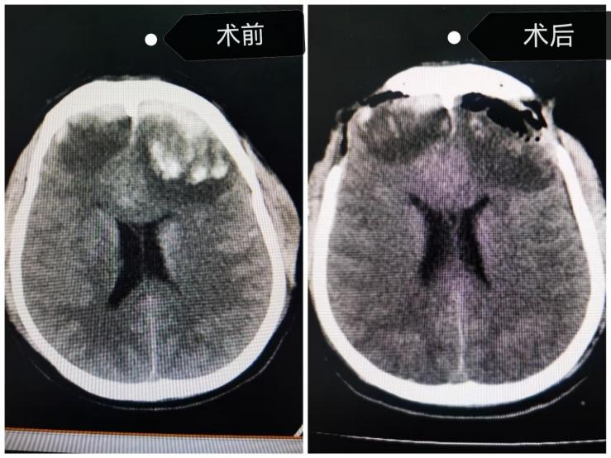

重症监护病房严密监护期间,医护人员发现江师傅意识障碍呈进行性加重。复查头部 CT 提示,患者脑挫裂伤及脑水肿情况较之前加重,出现脑疝症状。

神经外科团队评估后判定,患者具备明确手术指征。张化明主任向家属详细交代病情后,为患者实施脑内血肿清除术 + 双侧额骨去骨瓣减压术 + 颅内压监测术。手术顺利完成,术后复查头部 CT 显示,患者颅内血肿清除彻底,脑疝成功解除。